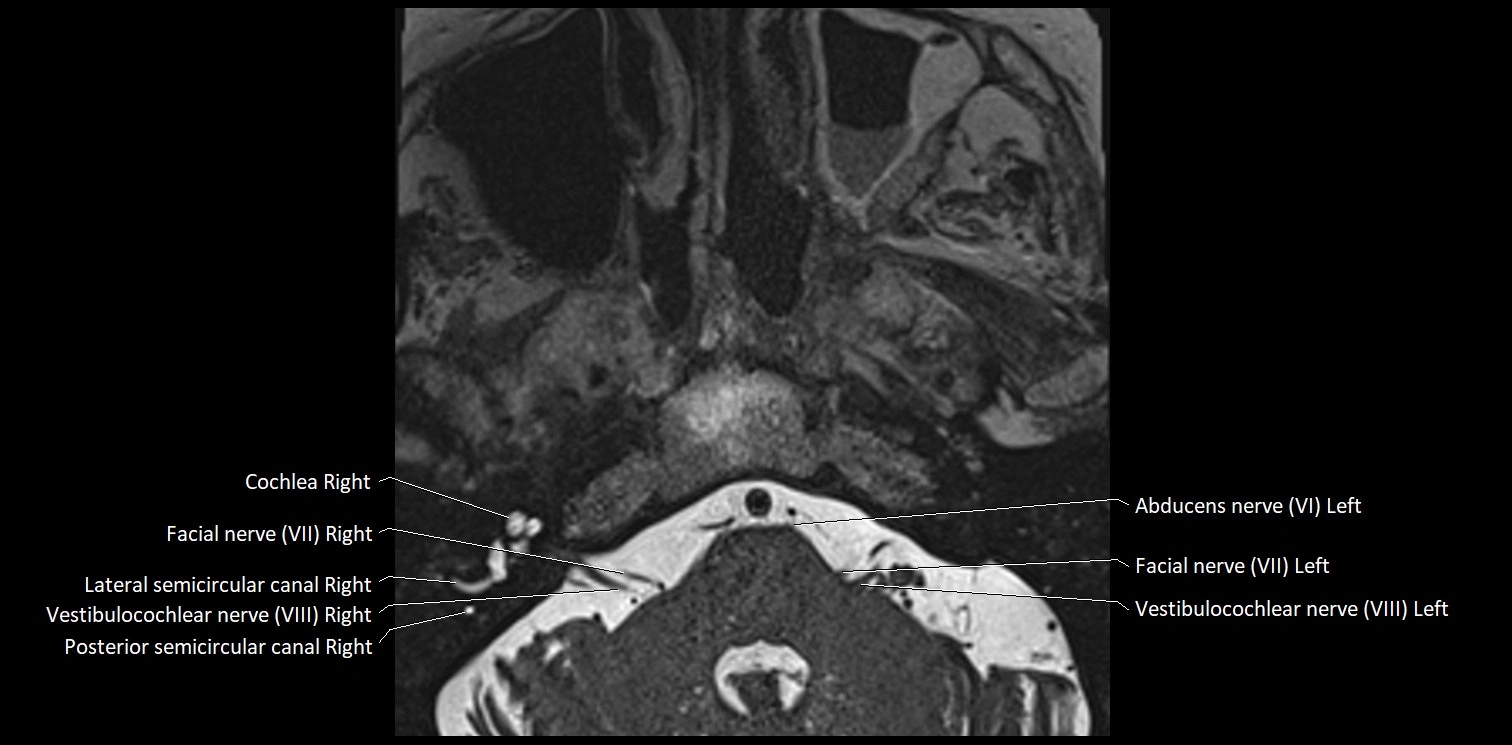

MRI Appearance

• The abducens nerve is a small, thin, linear structure

• Best visualized on high-resolution T2-weighted 3D MRI sequences (e.g., FIESTA or CISS)

• Seen as a hypointense (dark) line running from the brainstem at the pontomedullary junction, traversing the prepontine cistern, and entering Dorello’s canal under the petrosphenoidal ligament, then into the cavernous sinus, and finally the orbit

• May be challenging to visualize in standard MRI due to its small size

• Pathology may be inferred by absence, displacement, or enhancement of the nerve